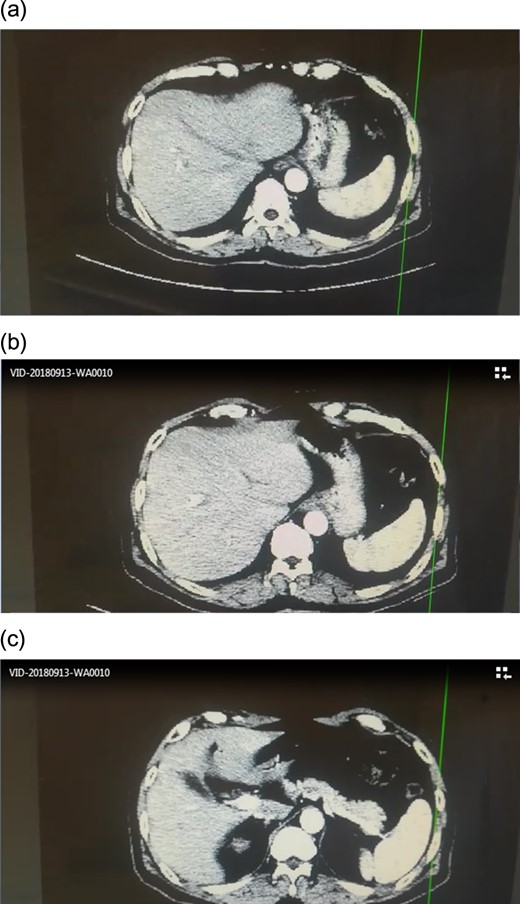

Angiographic CT after procedure confirmed the absence of celiac trunk, the absence of left gastric, the splenic artery arising from aorta directly and common hepatic artery arising from superior mesenteric artery.(Fig. 3)

In our case, there was no celiac trunk, no left gastric artery, the splenic artery emerged directly from the aorta and the common hepatic artery arising from Superior mesenteric artery. The surgical team completed the procedure despite this anomaly. The patient had a good recovery and a six-month follow up showed a person in acceptable health with no recurrence.